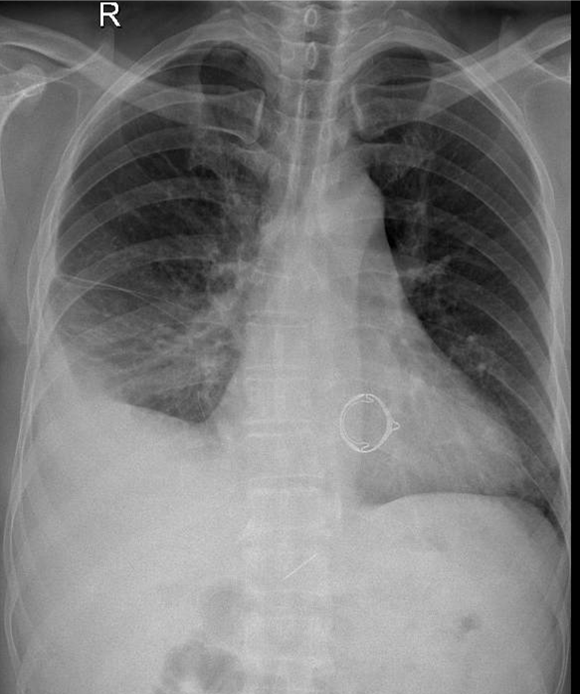

1-Thâm nhiễm phế nang lan tỏa thùy dưới phổi (P) => Viêm phổi 2-Tràn dịch màng phổi (P) lượng trung bình 3-Tim (T) lớn 4-Val tim nhân tạo